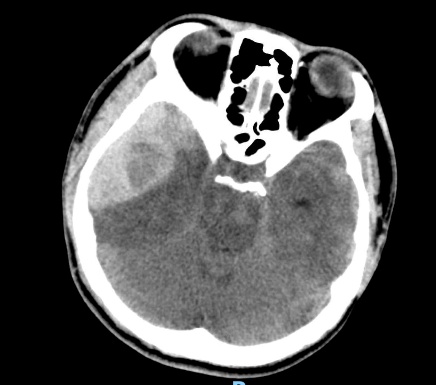

2.1. Xử lý hiệu quả các ca chấn thương sọ não: điều trị các ca chấn thương sọ não nặng Phẫu thuật các loại máu tụ nội sọ: ngoài màng cứng, máu tụ dưới màng cứng, máu tụ trong não,…

Phẫu thuật lấy máu tụ nội sọ